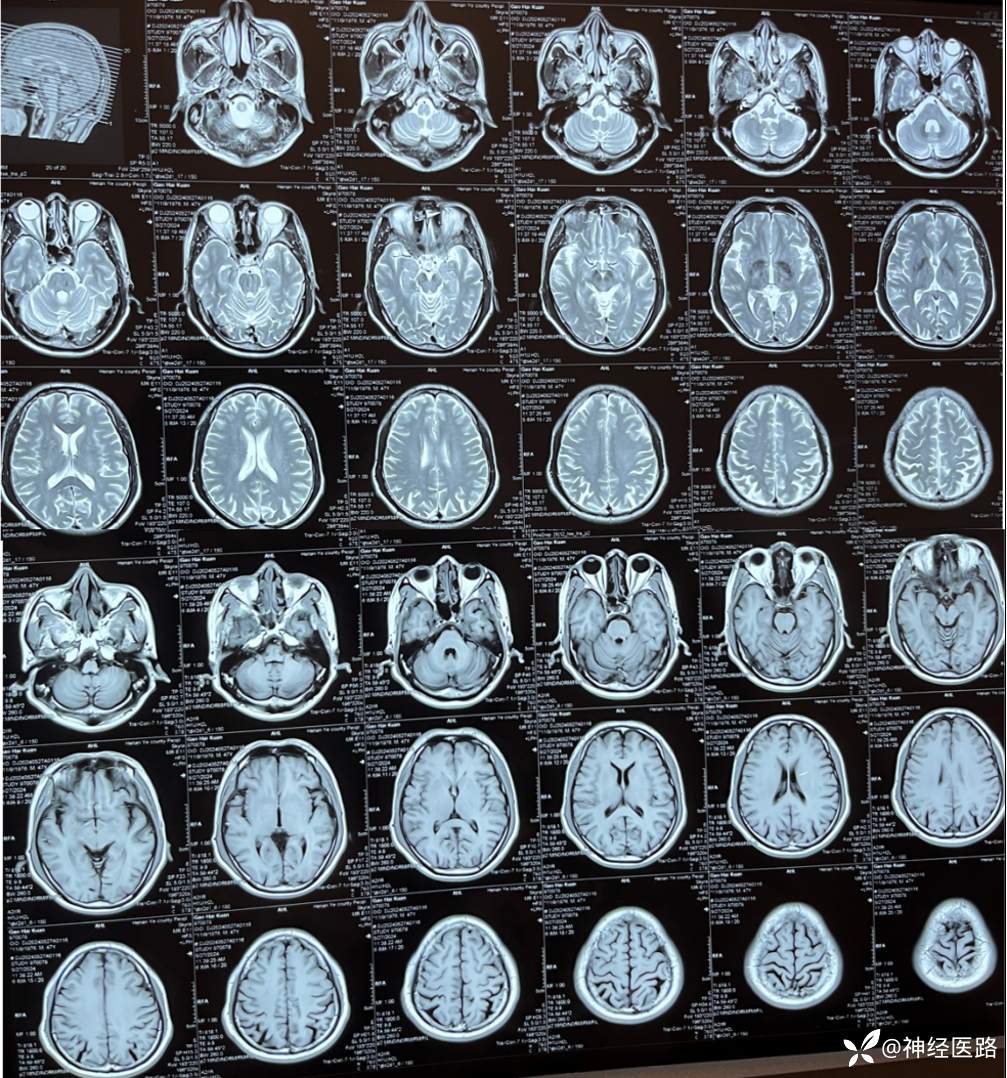

辅助检查:头部磁共振:1.颅脑DWI未见明显异常扩散受限。 2.脑白质高信号,脑萎缩。3.双侧上颌窦、双侧筛窦、双侧额窦炎。

补充1年余前直立倾斜试验、肌电图及头部磁共振检查资料。

两次影像对比